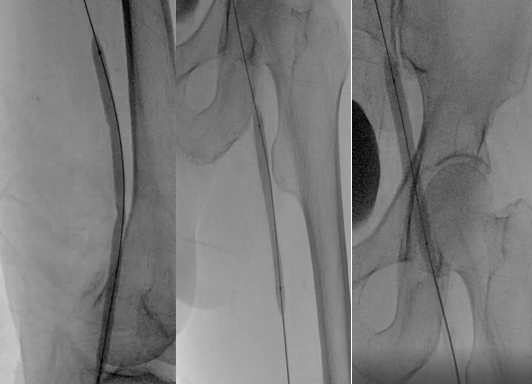

利用超滑导丝及微导丝反复尝试通过髂股静脉闭塞段引入球囊扩张导管行髂股静脉球囊扩张成形,扩张过程中可见明显切迹。

球囊扩张后支架定位,透视下释放14×140mm支架2枚,术后评估支架扩张良好,支架头端定位伸入下腔静脉5mm左右,未覆盖右侧髂总静脉开口。